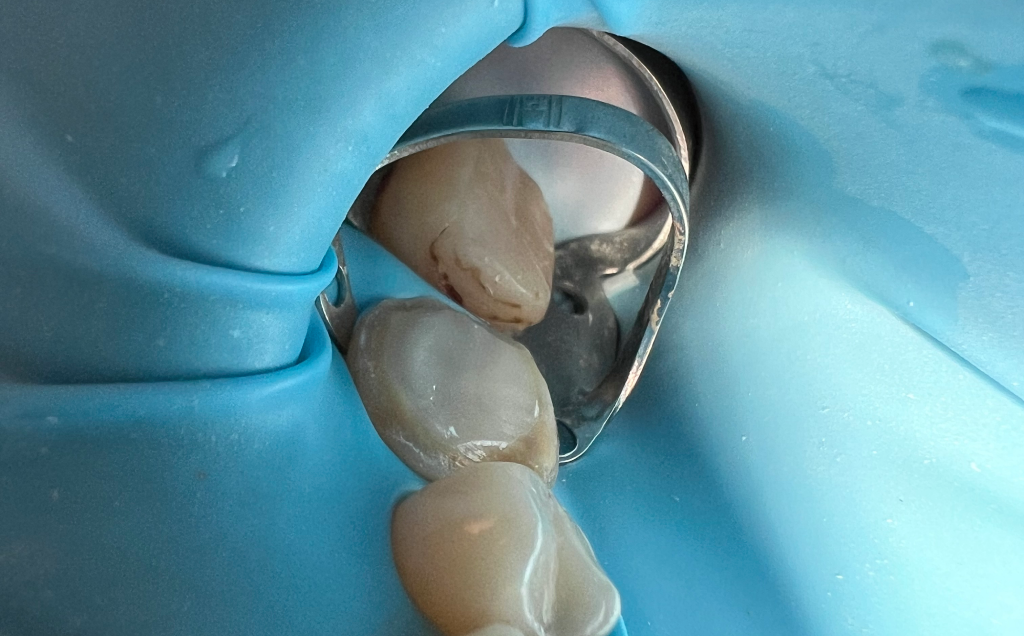

Leczenie biologiczne - żadna część zakażonej tkanki zęba nie dostaje się do tkanek zdrowych.